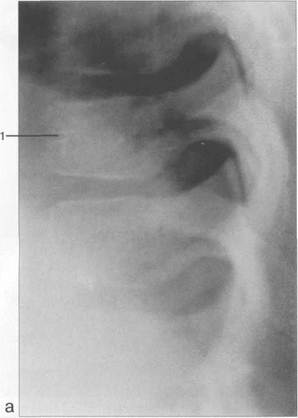

а— боковая проекция:1 — передняя дуга атланта; 2 — зуб С„; 3 — боковая масса Ct; 4 — задняя дуга С,; 5 — тело позвонка; 6 — поперечный отросток; 7 — нижний суставной отросток; 8 — верхний суставной отросток; 9 — пластина дуги; 10 — закладка остистого отростка; 11 — ножка дуги.

6 — прямая проекция:1 — зуб С„; 2 — задняя дуга С,; 3 — верхняя суставная поверхность боковой массы Ср - 4 — нижняя суставная поверхность боковой массы Ct; 5 — поперечный отросток Ср 6 — нижний суставной отросток Сп;

7 — верхняя суставная поверхность Сп; 8 — тело Сн; 9 — пластина дуги; 10 — верхний суставной отросток; 11 — нижний суставной отросток; 12 — ножка дуги; 13 — тело позвонка.

Рис. 3.1. Рентгенограммы шейного отдела позвоночника новорожденного и схемы.